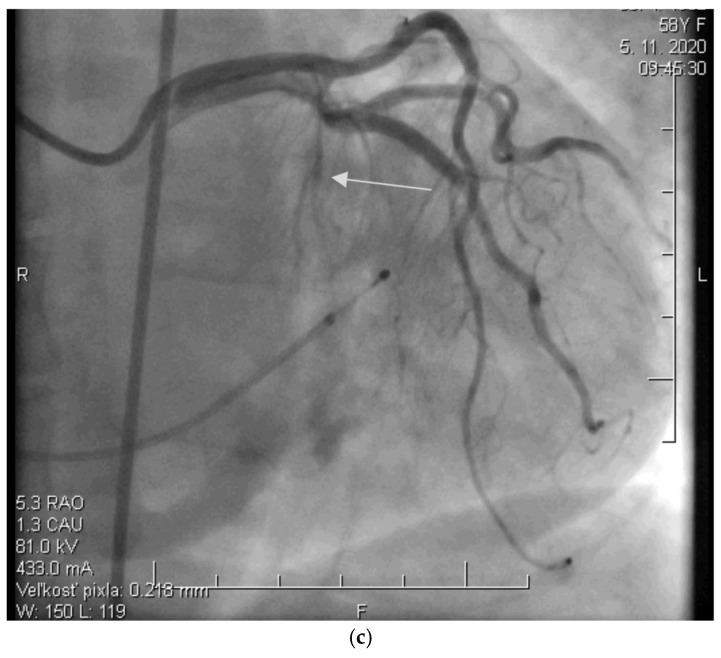

背景/目的:本研究旨在探讨肥厚性心肌病(HCM)患者右心室(RV)结构和功能之间的关系,并建立酒精间隔消融术(ASA)疗效的标志物。我们假设右心室特征可以作为ASA后早期左心室流出道梯度(LVOTG)的预测因子。方法:对50例接受ASA治疗的HCM患者进行回顾性分析。在术后3个月、1年、3年和5年评估超声心动图RV参数与ASA成功标准指标的相关性。结果:ASA后3个月和1年的左室壁厚(RVWT)与最大LVOTG (p < 0.001)、NYHA功能分级和左室舒张末期尺寸(LVD)均有显著相关性(p < 0.01)。在第3年和第5年,这些相关性不再具有统计学意义(p = ns)。其他参数未观察到关联。结论:超声心动图评估RVWT可作为ASA后3个月LVOTG发展的早期预测指标。因此,RVWT可以提供长期治疗效果的估计。需要进一步的研究来证实这些发现。

Background/Objectives: This study aimed to investigate the association between right ventricular (RV) structure and function and established markers of alcohol septal ablation (ASA) efficacy in patients with hypertrophic cardiomyopathy (HCM). We hypothesized that RV characteristics may serve as predictors of left ventricular outflow tract gradient (LVOTG) in the early period following ASA. Methods: A retrospective analysis was performed in 50 HCM patients who underwent ASA. Correlations between echocardiographic RV parameters and standard indicators of ASA success were assessed at 3 months, 1 year, 3 years, and 5 years post-procedure. Results: Echocardiographic measurements of RV wall thickness (RVWT) at 3 months and 1 year after ASA showed significant correlations with maximum LVOTG (p < 0.001), NYHA functional class, and left ventricular end-diastolic dimension (LVD) (both p < 0.01). At 3 and 5 years, these correlations were no longer statistically significant (p = ns). No associations were observed for other parameters. Conclusions: Echocardiographic assessment of RVWT may serve as an early predictor of subsequent LVOTG development as soon as 3 months after ASA. RVWT could therefore provide an estimate of long-term treatment effects. Further studies are needed to confirm these findings.